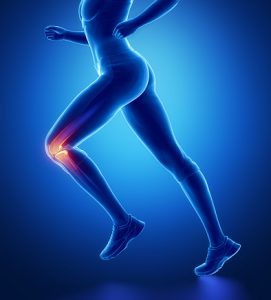

Creaky knees are often described as a crunchy sound emanated when you bend at the knee joints. Sometimes, your knees may look puffy or swollen but it doesn’t present with pain. Our knees are used practically every day during movements like walking, running, jumping, and climbing. The more we bend our knees, the more we may notice that they are making a creaking sound.

Creaky knees are often described as a crunchy sound emanated when you bend at the knee joints. Sometimes, your knees may look puffy or swollen but it doesn’t present with pain. Our knees are used practically every day during movements like walking, running, jumping, and climbing. The more we bend our knees, the more we may notice that they are making a creaking sound.

The medical term for creaky joints is called “crepitus,” which can be heard as well as felt when placing your hand over the affected joint and moving it. A big joint, such as our knees, have cartilage designed to act as a cushion between bones. If this cartilage were to become damaged or worn out, the bones in the joint will begin to rub up against each other, possibly creating a creaky sound.

Depending on the underlying condition, creaky knee joints may also present with pain and swelling.

Direct trauma to the ligaments, meniscus, or soft tissues of the knee can cause damage to the supporting cartilage. An injury to any of these knee structures can make it difficult to bear weight on that side of the body and possibly cause the knee to produce a creaky sound due to the loss of cushioning.

Natural wear and tear in combination with the decreased ability to heal ourselves as we get older can contribute to the gradual degradation of knee cartilage. This can make moving the knee joints painful and difficult. This is commonly seen in a condition called osteoarthritis, which commonly presents with creaky knees.

A biotechnical problem caused by a misaligned kneecap (patella). This often results in the kneecap sitting too high in the femoral groove or dislocating easily, which may allow it to rub up against the thigh bone (femur), leading to creaky knees. This condition does not necessarily need to be caused by running or excessive exercise, as a direct injury or having flat feet can change the alignment of your kneecap and cause pain and creaking.